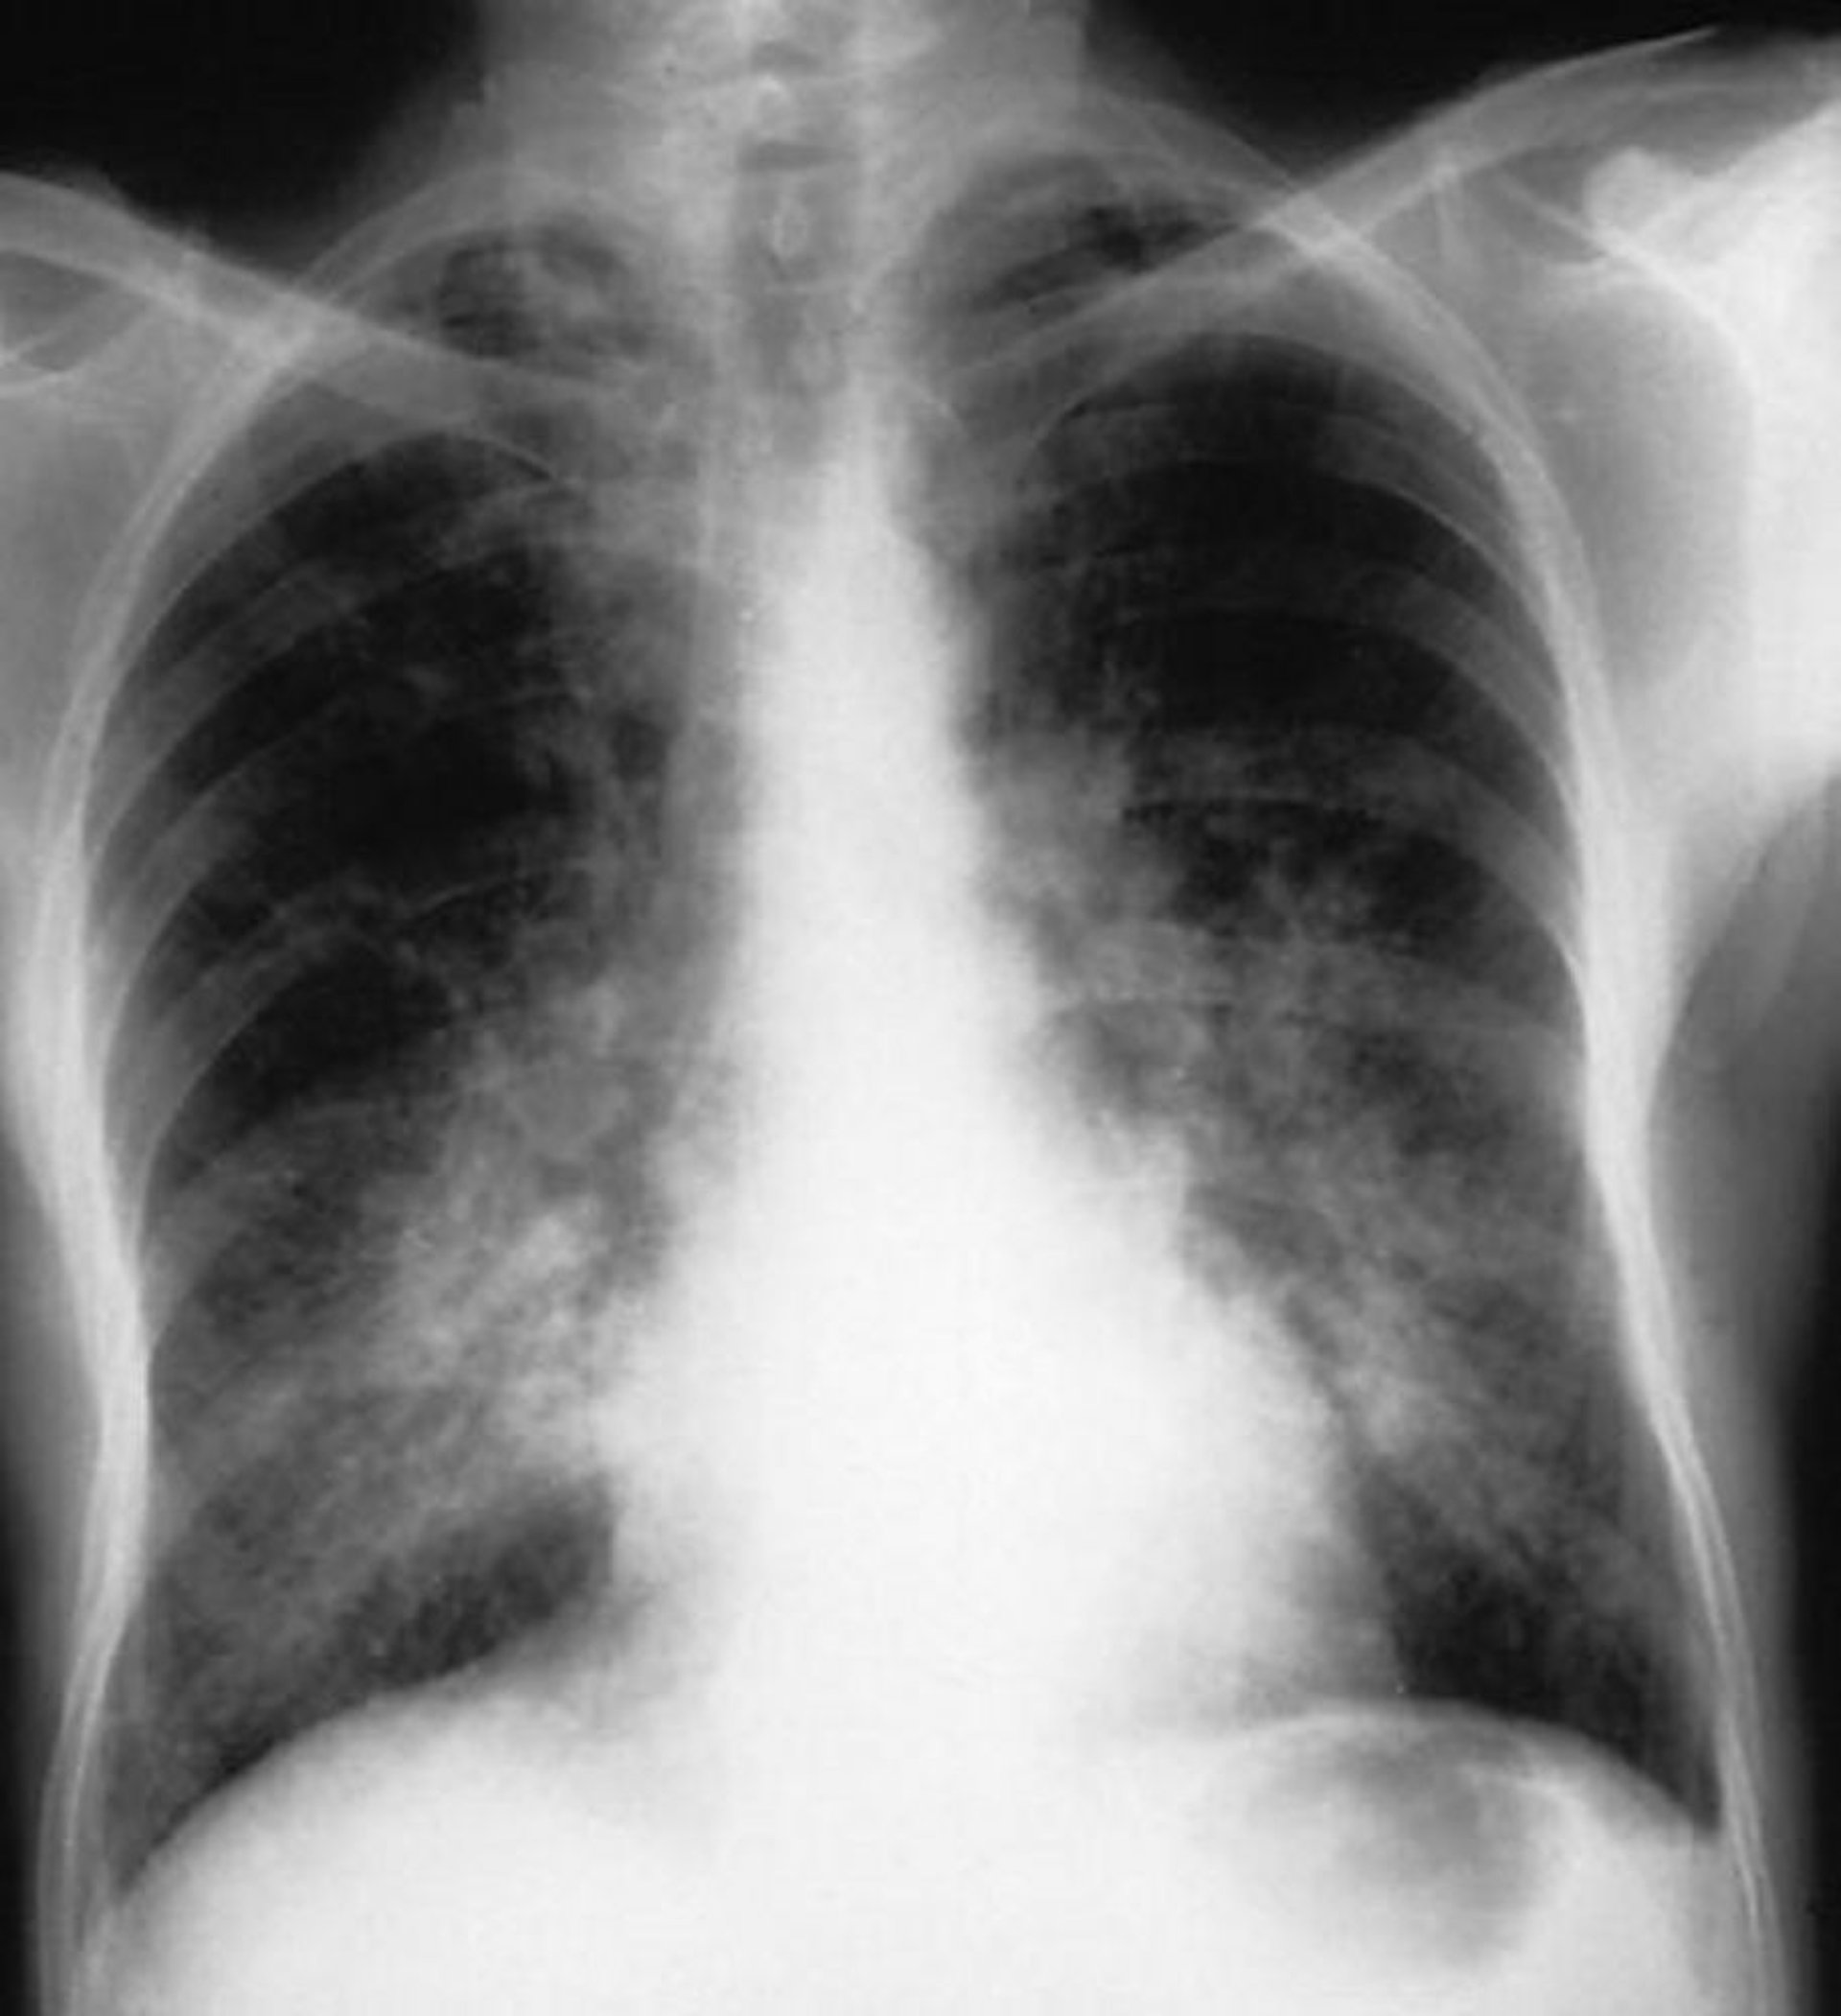

Xuất huyết phế nang (Hội chứng Goodpasture)

Các đám mờ phế nang hai bên ở một bệnh nhân bị xuất huyết phế nang do hội chứng Goodpasture.

Được sự cho phép của nhà xuất bản. Theo Cohen A, Glassock R. Trong Atlas of Diseases of the Kidney: Glomerulonephritis and Vasculitis. Biên tập bởi R Schrier (biên tập loạt bài), RJ Glassock và AH Cohen. Philadelphia, Current Medicine, 1999.